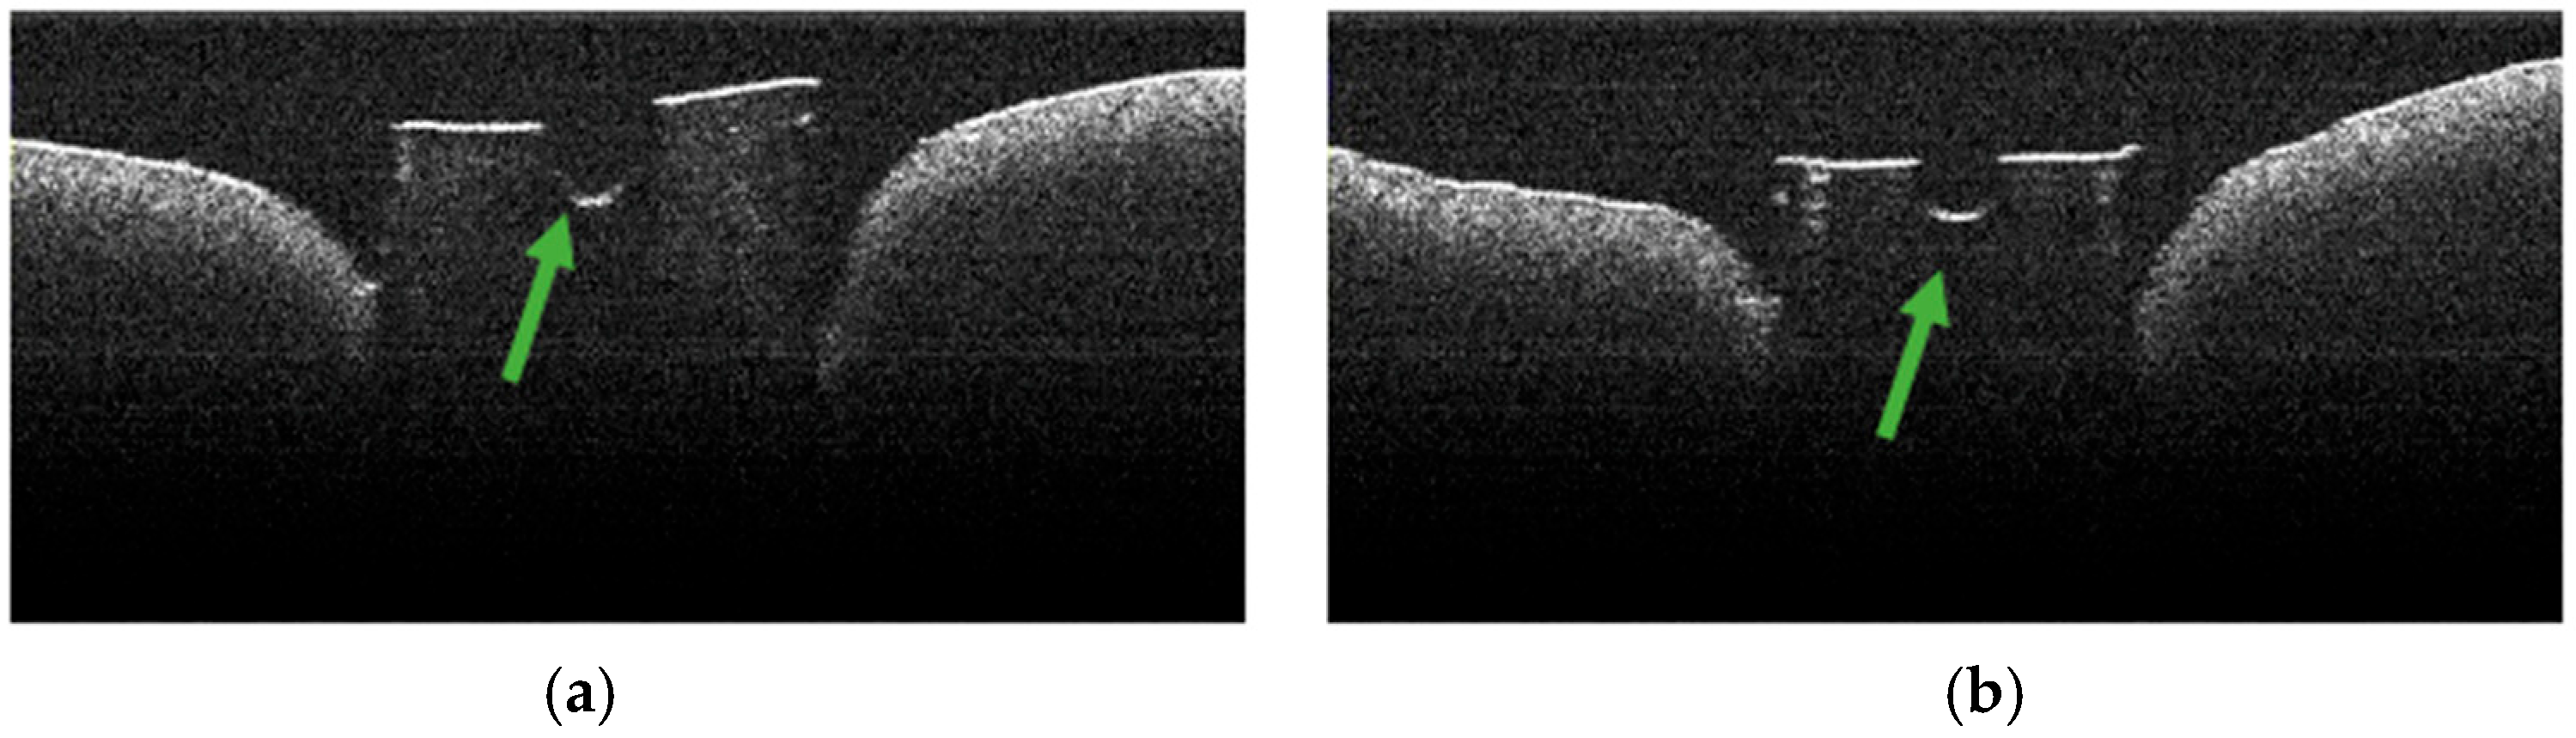

3.5. OCT Examination of Specimens from Group B

3.2. Defining OCT Signatures: Alterations vs. Artefacts

3.7. Frequency of TIMAs